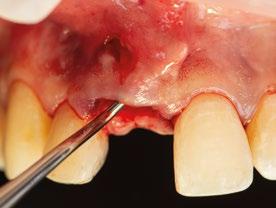

3.- Legramos toda la zona del lecho implantario con el fin de poder eliminar cualquier resto de tejido de granulación.

4.- Desepitelizamos en margen gingival. (Figura 17)